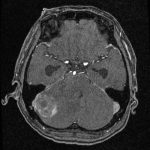

摘出 後